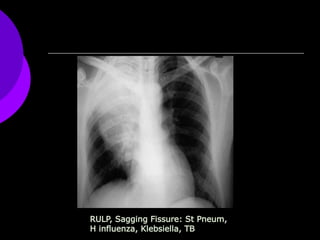

RULP, Sagging Fissure: St Pneum,

H influenza, Klebsiella, TB

RULP, Sagging Fissure:St Pneum, H influenza, Klebsiella, TB